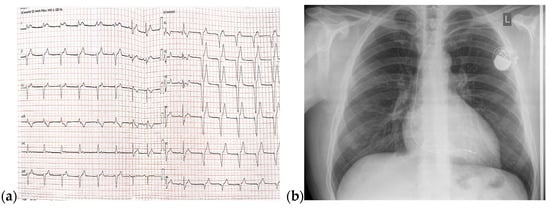

On admission, a TTE was performed and confirmed Ebstein’s anomaly. The main findings of the TTE were non-dilated left ventricle with an ejection fraction of 50% evaluated using Simpson’s method, dilated right chambers, atrialization of the RV, apical insertion of the septal cusp of the tricuspid valve, and mild functional tricuspid regurgitation (Figure 8).

Figure 8.

TTE on admission: (a) Apical 4-chamber view: dilated right cavities with a RV diameter of 7, 3 cm; (b) Apical 4-chamber view: total volume of the RV—252 mL; (c) Apical 4-chamber view: functional RV volume—170 mL; (d) Apical 4-chamber view: atrialized RV volume—123 mL; Abbreviations: TTE—transthoracic echocardiography; RV—right ventricle.

The follow-up TTE evaluation demonstrated a nondilated left ventricle with preserved ejection fraction, dilated right chambers, an increased total volume of RV measuring 339 mL and atrialized RV with a volume of 135 mL, severe functional tricuspid regurgitation, insertion of the septal cusp of the tricuspid valve approximately 2.9 cm from the plane of the tricuspid annulus and ventricular pacing electrode (Figure 12).

Figure 12.

The TTE follow-up evaluation: (a) Apical 4-chamber view: dilated right cavities with a total volume of RV measuring 339 mL; (b) Apical 4-chamber view: atrialized RV volume of 135 mL; (c) Apical 4-chamber view: color Doppler flow revealing severe tricuspid regurgitation; (d) Tricuspid continuous wave Doppler flow: maximum RV-RA gradient = 33.45 mmHg; (e) Apical 4-chamber view: insertion of the septal cusp of the tricuspid valve at approximately 2.9 cm from the plane of the tricuspid annulus; (f) Apical 4-chamber view: end-diastolic left ventricular volume—110 mL. Abbreviations: TTE—transthoracic echocardiography; RV—right ventricle, RA—right atrium.